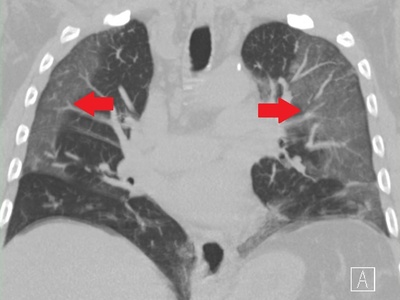

COVID-19

COVID-19 is caused by SARS-CoV-2, commonly producing fever, cough, fatigue and loss of smell; severe cases cause pneumonia and long-term symptoms. Global since 2019; spreads by respiratory routes. Vaccines and masks reduce risk; treatments and antivirals available for high-risk patients.